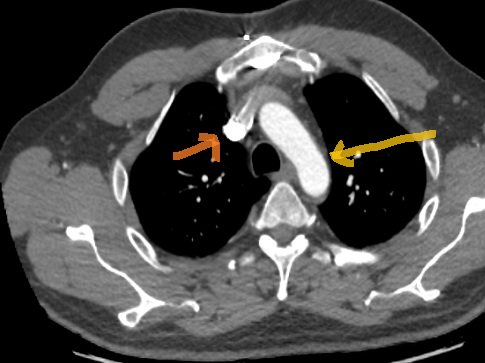

Du coup là la flèche orange clair c'est la crosse de l'aorte et la flèche orange foncé c'est la veine jugulaire interne ??

Image

Reste juste à m'aider pour la flèche orange foncé du deuxième scanner, merci !

La flèche orange foncée, c'est tout simplement la veine cave supérieure, non ? :)